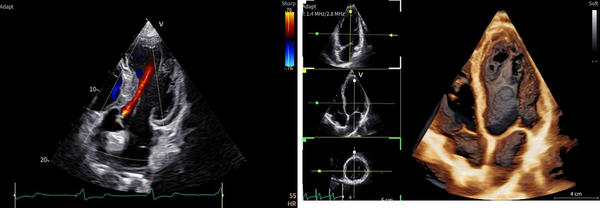

「Vivid Pioneer」は,これまで検査者が手作業で行っていた血流解析をAIが自動で行い,短時間で安定した測定プロセスを提供する。また,心臓の主要な部位(左心室と左心房)の動きや形を三次元で自動分析し,検査者間の標準化を支援する。そのほか,次世代の画像エンジン機能により,細部の見やすさ(空間分解能)や色の見やすさ(カラー感度)が向上し,より高精度な心臓の立体画像を描出する。

AIが血流を自動解析

次世代の画像エンジンによる高精細な心臓画像